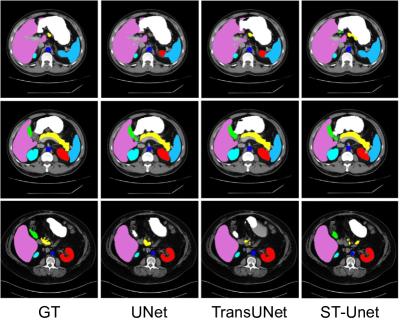

Refer to caption

Figure 11: Segmentation results on the Synapse dataset [256] using UNet, TransUNet [193], and ST-Unet [376].